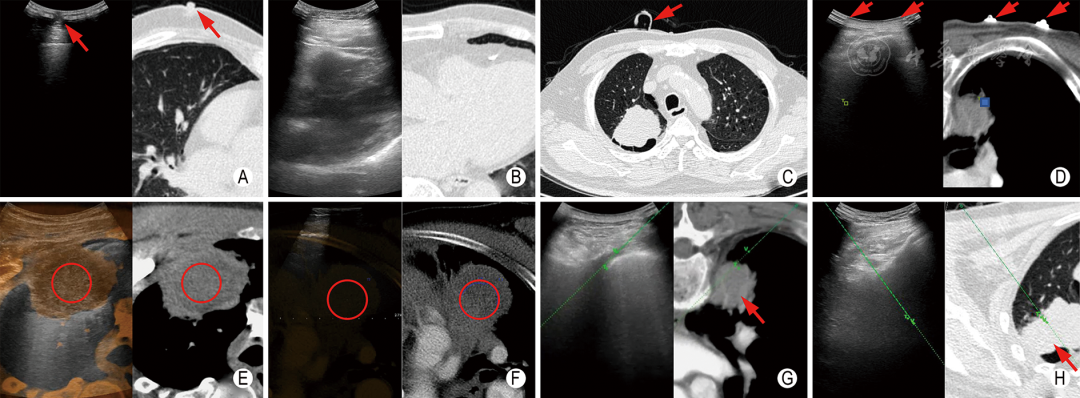

1.选择不被骨性结构阻挡,不经过大血管、重要脏器、含气肺组织及充气支气管等的穿刺路径,且超声可清晰显示穿刺路径全程(图5A,B)。

图5  术中操作 A:灰阶超声显示病灶内含有局限性支气管充气征,红色箭头标记的穿刺路径会经过支气管,增加气胸、空气栓塞和咯血的风险,白色箭头标记的路径更安全; B:CDFI显示病灶内有粗大血管,红色箭头标记的穿刺路径会经过血管,增加出血的风险,白色箭头标记的路径更安全; C:超声造影显示病灶内存在坏死区(无增强区),红色箭头标记的穿刺路径经过坏死区,不利于病理诊断,白色箭头标记的路径更有可能获得有活性的病理样本; D~F:超声显示麻药在胸膜表面扩散(红色箭头所示); G:同轴定位针及配套全自动活检针,α为同轴定位针的长度,β为活检针击发射程; H:在超声引导下将同轴定位针置入病灶,针尖前方留有足够的活检距离; I:全自动活检针经同轴定位针置入病灶内并前向切割取材

2.有条件的情况下可行超声造影检查,识别病灶内有活性、恶性可能性高的区域进行取材(图5C)。

穿刺前均应建立静脉通路,必要时监测心电、血压和血氧饱和度。常规消毒、铺巾,使用无菌隔离套包裹超声探头。采用2%利多卡因溶液在超声引导下对穿刺点进行局部逐层浸润麻醉,重点麻醉壁层胸膜,剂量常用5 ml,可根据麻醉效果及进针深度适当增加(图5E~G)。

(五)同轴技术

病灶较大,可为切割式活检针保留足够的击发射程时,可将同轴定位针尖置于病灶内,不仅可减少因空气经同轴定位针进入负压状态的胸腔导致的气胸,还可以避免穿刺针反复经过胸膜导致的出血和疼痛(图5H~J)。当病灶较小,预估击发后针尖会进入深部肺组织时,同轴定位针也可置于胸壁肌层,并根据病灶大小和击发射程调整位置。